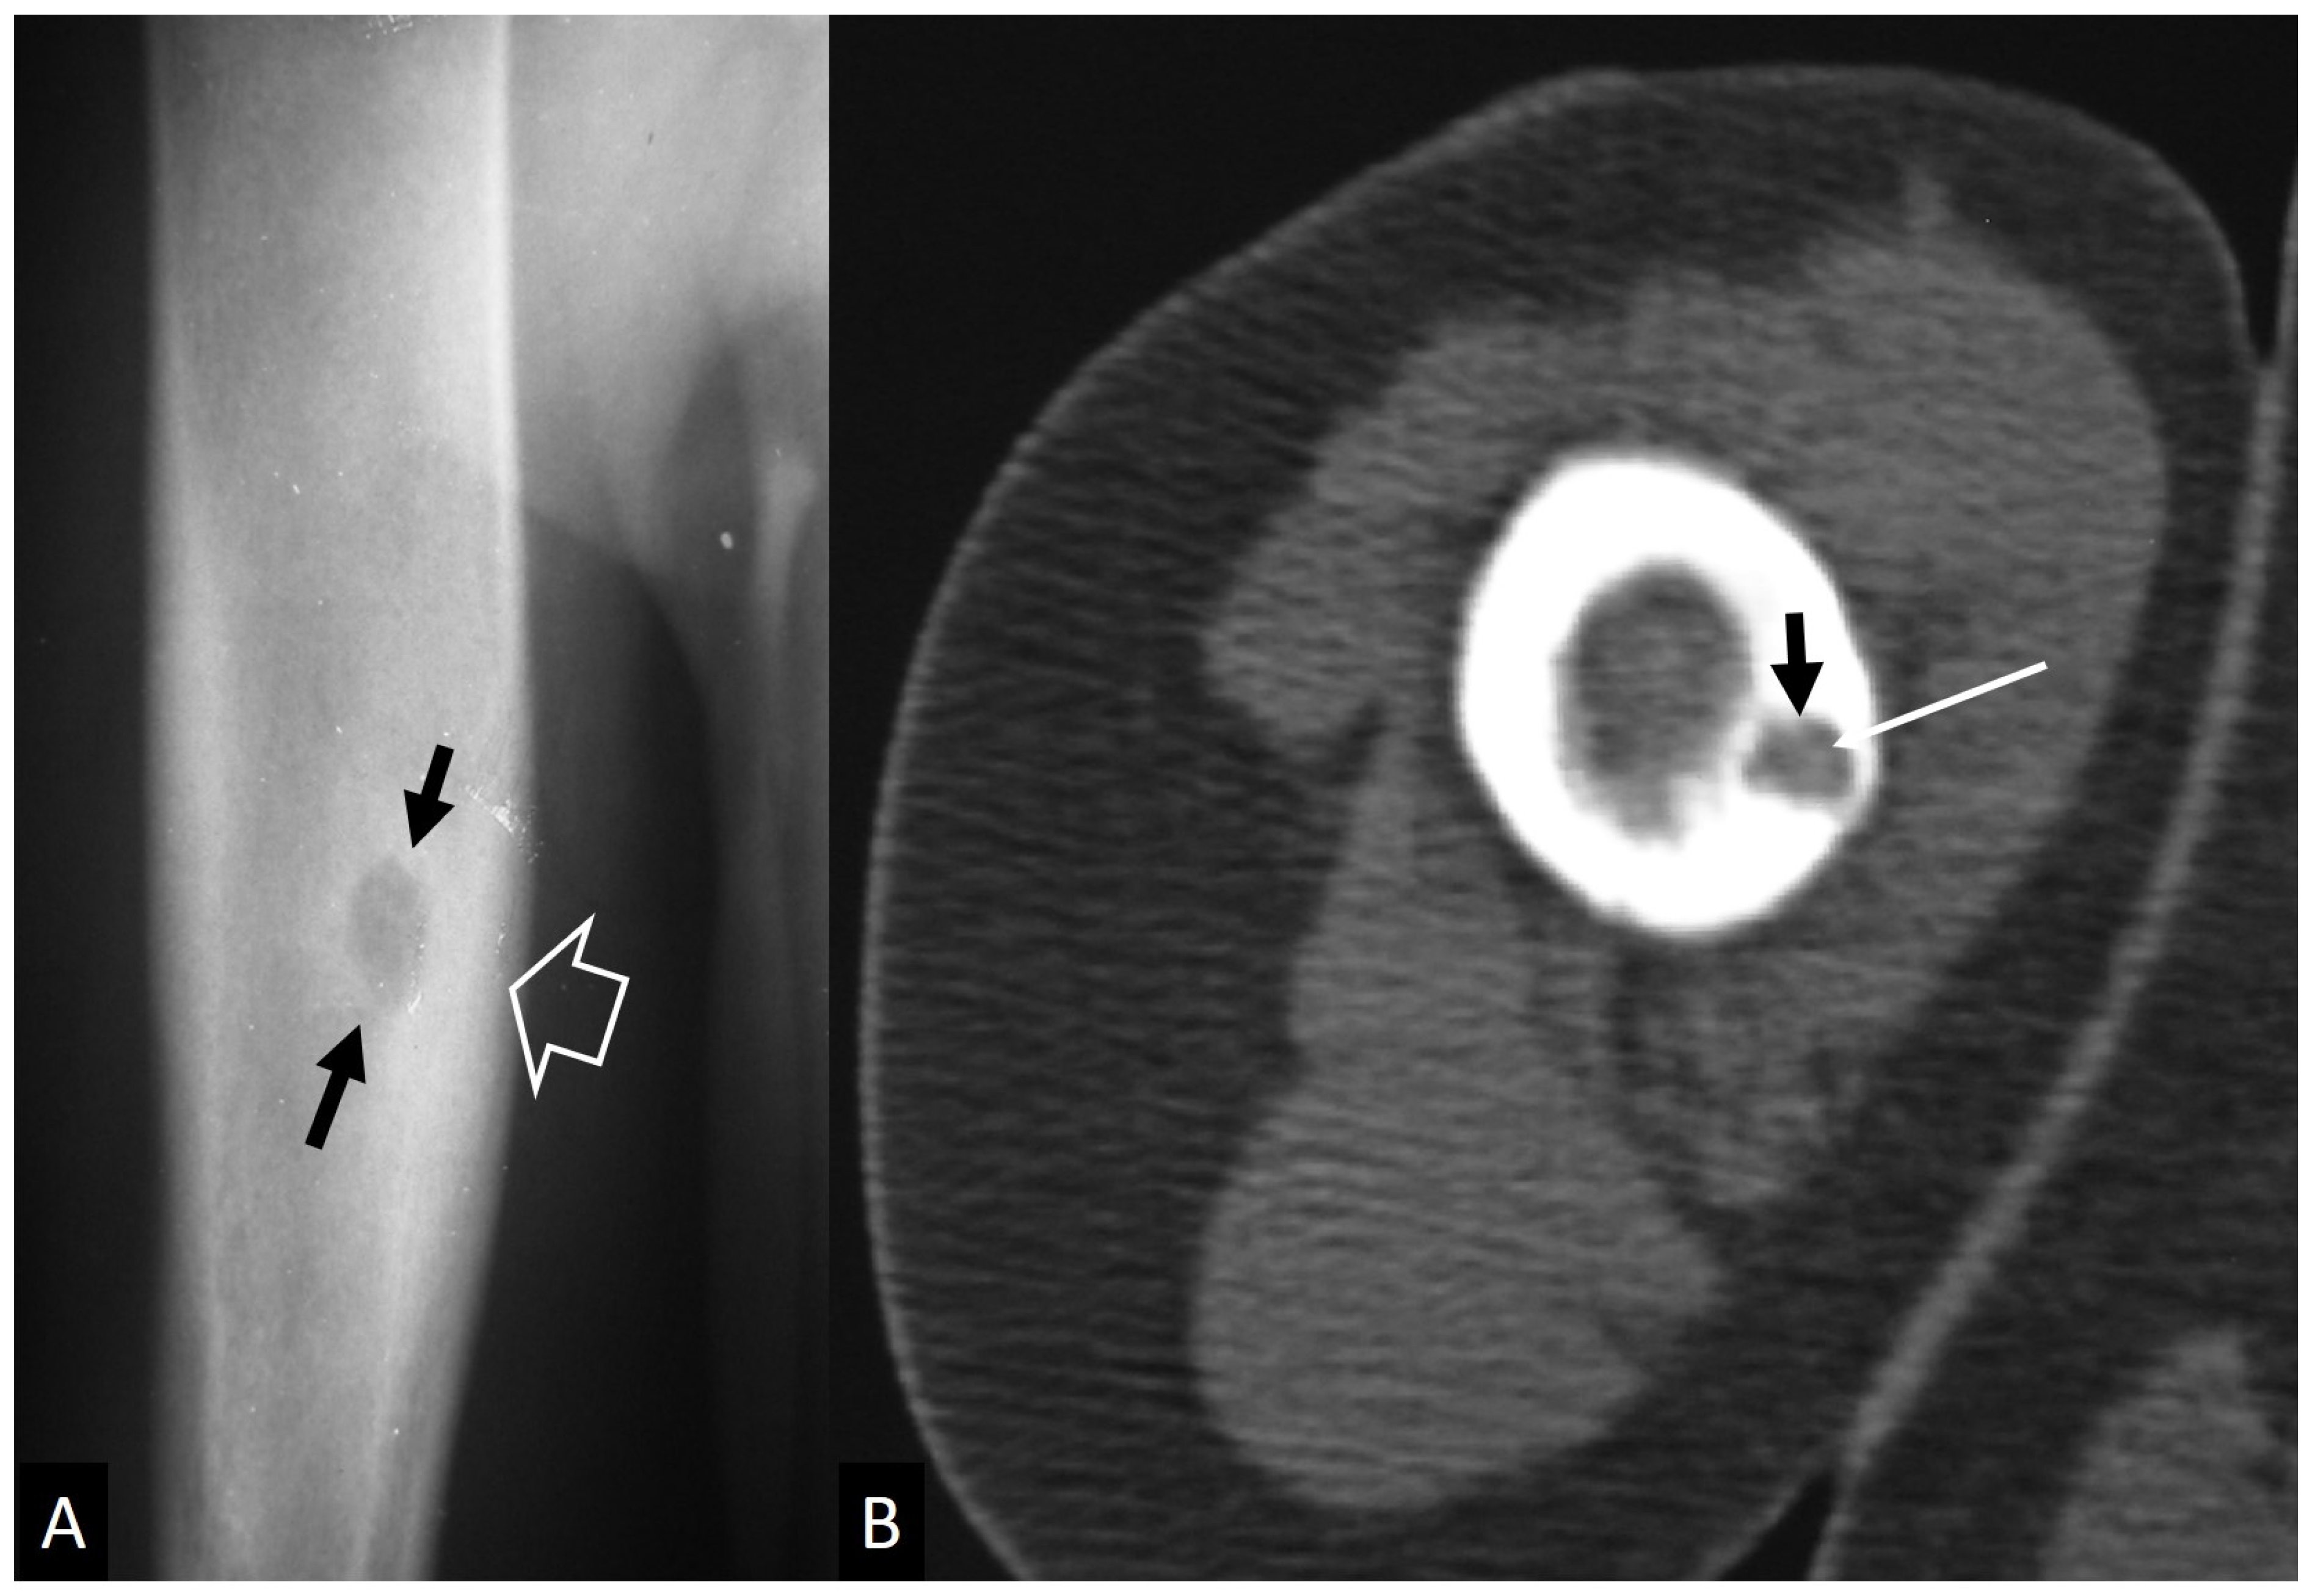

3.2.1. Ewing’s Sarcoma

- Henninger, B.; Glodny, B.; Rudisch, A.; Trieb, T.; Loizides, A.; Putzer, D.; Judmaier, W.; Schocke, M.F. Ewing sarcoma versus osteomyelitis: Differential diagnosis with magnetic resonance imaging. Skelet. Radiol. 2013, 42, 1097–1104. [Google Scholar] [CrossRef]

- McCarville, M.B.; Chen, J.Y.; Coleman, J.L.; Li, Y.; Li, X.; Adderson, E.E.; Neel, M.D.; Gold, R.E.; Kaufman, R.A. Distinguishing Osteomyelitis from Ewing Sarcoma on Radiography and MRI. AJR Am. J. Roentgenol. 2015, 205, 640–650, quiz 651. [Google Scholar] [CrossRef]

- Mulligan, M.E.; McRae, G.A.; Murphey, M.D. Imaging features of primary lymphoma of bone. AJR Am. J. Roentgenol. 1999, 173, 1691–1697. [Google Scholar] [CrossRef] [PubMed]

- Krishnan, A.; Shirkhoda, A.; Tehranzadeh, J.; Armin, A.R.; Irwin, R.; Les, K. Primary bone lymphoma: Radiographic-MR imaging correlation. Radiographics 2003, 23, 1371–1383, discussion 1384–1387. [Google Scholar] [CrossRef]

- Mulligan, M.E.; Kransdorf, M.J. Sequestra in primary lymphoma of bone: Prevalence and radiologic features. AJR Am. J. Roentgenol. 1993, 160, 1245–1248. [Google Scholar] [CrossRef]